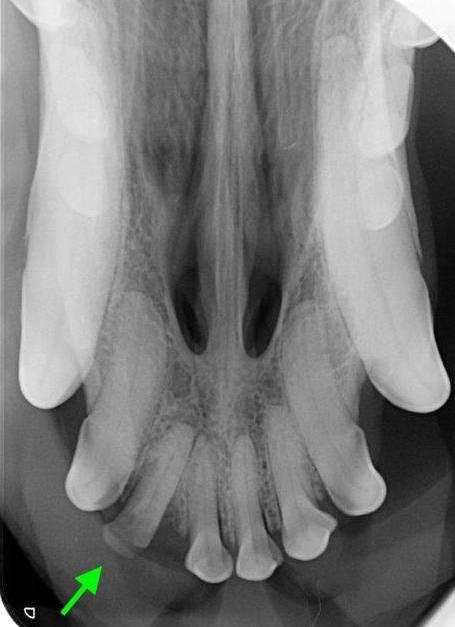

Der hübsche neun Jahre alte schwarze Mischlingsrüde Nando aus Italien wird vorgestellt, da die Besitzerin Zahnstein und einen unangenehmen Geruch aus der Maulhöhle festgestellt hat. Während der Untersuchung werden folgende Befunde erhoben: mittelgradiger Zahnstein an den meisten Zähnen, im Unter- und Oberkiefer je ein abgebrochener Schneidezahn (Abb. 1 und 2) und eine große „Zahnlücke“ im Unterkiefer rechts (Abb. 3). Hier scheinen die drei letzten Backenzähne zu fehlen. Nando ist ein sportlicher und schlanker Hund. Sein Herz schlägt regelmäßig und ohne Nebengeräusche. Dennoch untersuchen wir vor der Operation sein Blut, um mögliche Anästhesierisiken weitgehend ausschließen zu können. Wenige Tage später werden Nandos Zähne in Narkose sorgfältig von Zahnstein befreit und anschließend poliert. Von den beiden abgebrochenen Schneidezähnen und dem Bereich der vermeintlichen Zahnlücke im Unterkiefer werden Röntgenbilder angefertigt. Die Kronen der beiden Schneidezähne sind so tief abgebrochen, dass die Pulpahöhle offen liegt (Abb. 4). Im Bereich der „Zahnlücke“ zeigt das Röntgenbild Wurzelanteile nicht vollständig vorhandener oder vielleicht auch nicht vollständig ausgebildeter Zähne (Abb. 5).

In der Pulpa verlaufen die Blut- und Nervengefässe eines Zahnes. Da die Schneidezähne von „Nando“ so tief abgebrochen sind, dass Blut und Nervengefäße nicht mehr durch die Schicht des Dentins und des Zahnschmelzes vor einem Kontakt mit der Außenwelt geschützt sind, ist eine Behandlung unbedingt erforderlich. Denn zum einen besteht die Gefahr einer Infektion, und zum anderen ist beim Tier in diesem Fall genauso wie beim Mensch mit Zahnschmerzen zu rechnen. Eine aufwändige Wurzelbehandlung, die für abgebrochene oder anderweitig erkrankte Zähne auch beim Tier möglich ist, scheint im Fall der funktionell wenig bedeutsamen Schneidezähne nicht gerechtfertigt. Daher ziehen wir bei „Nando“ die beiden abgebrochenen Schneidezähne in der Vollnarkose.